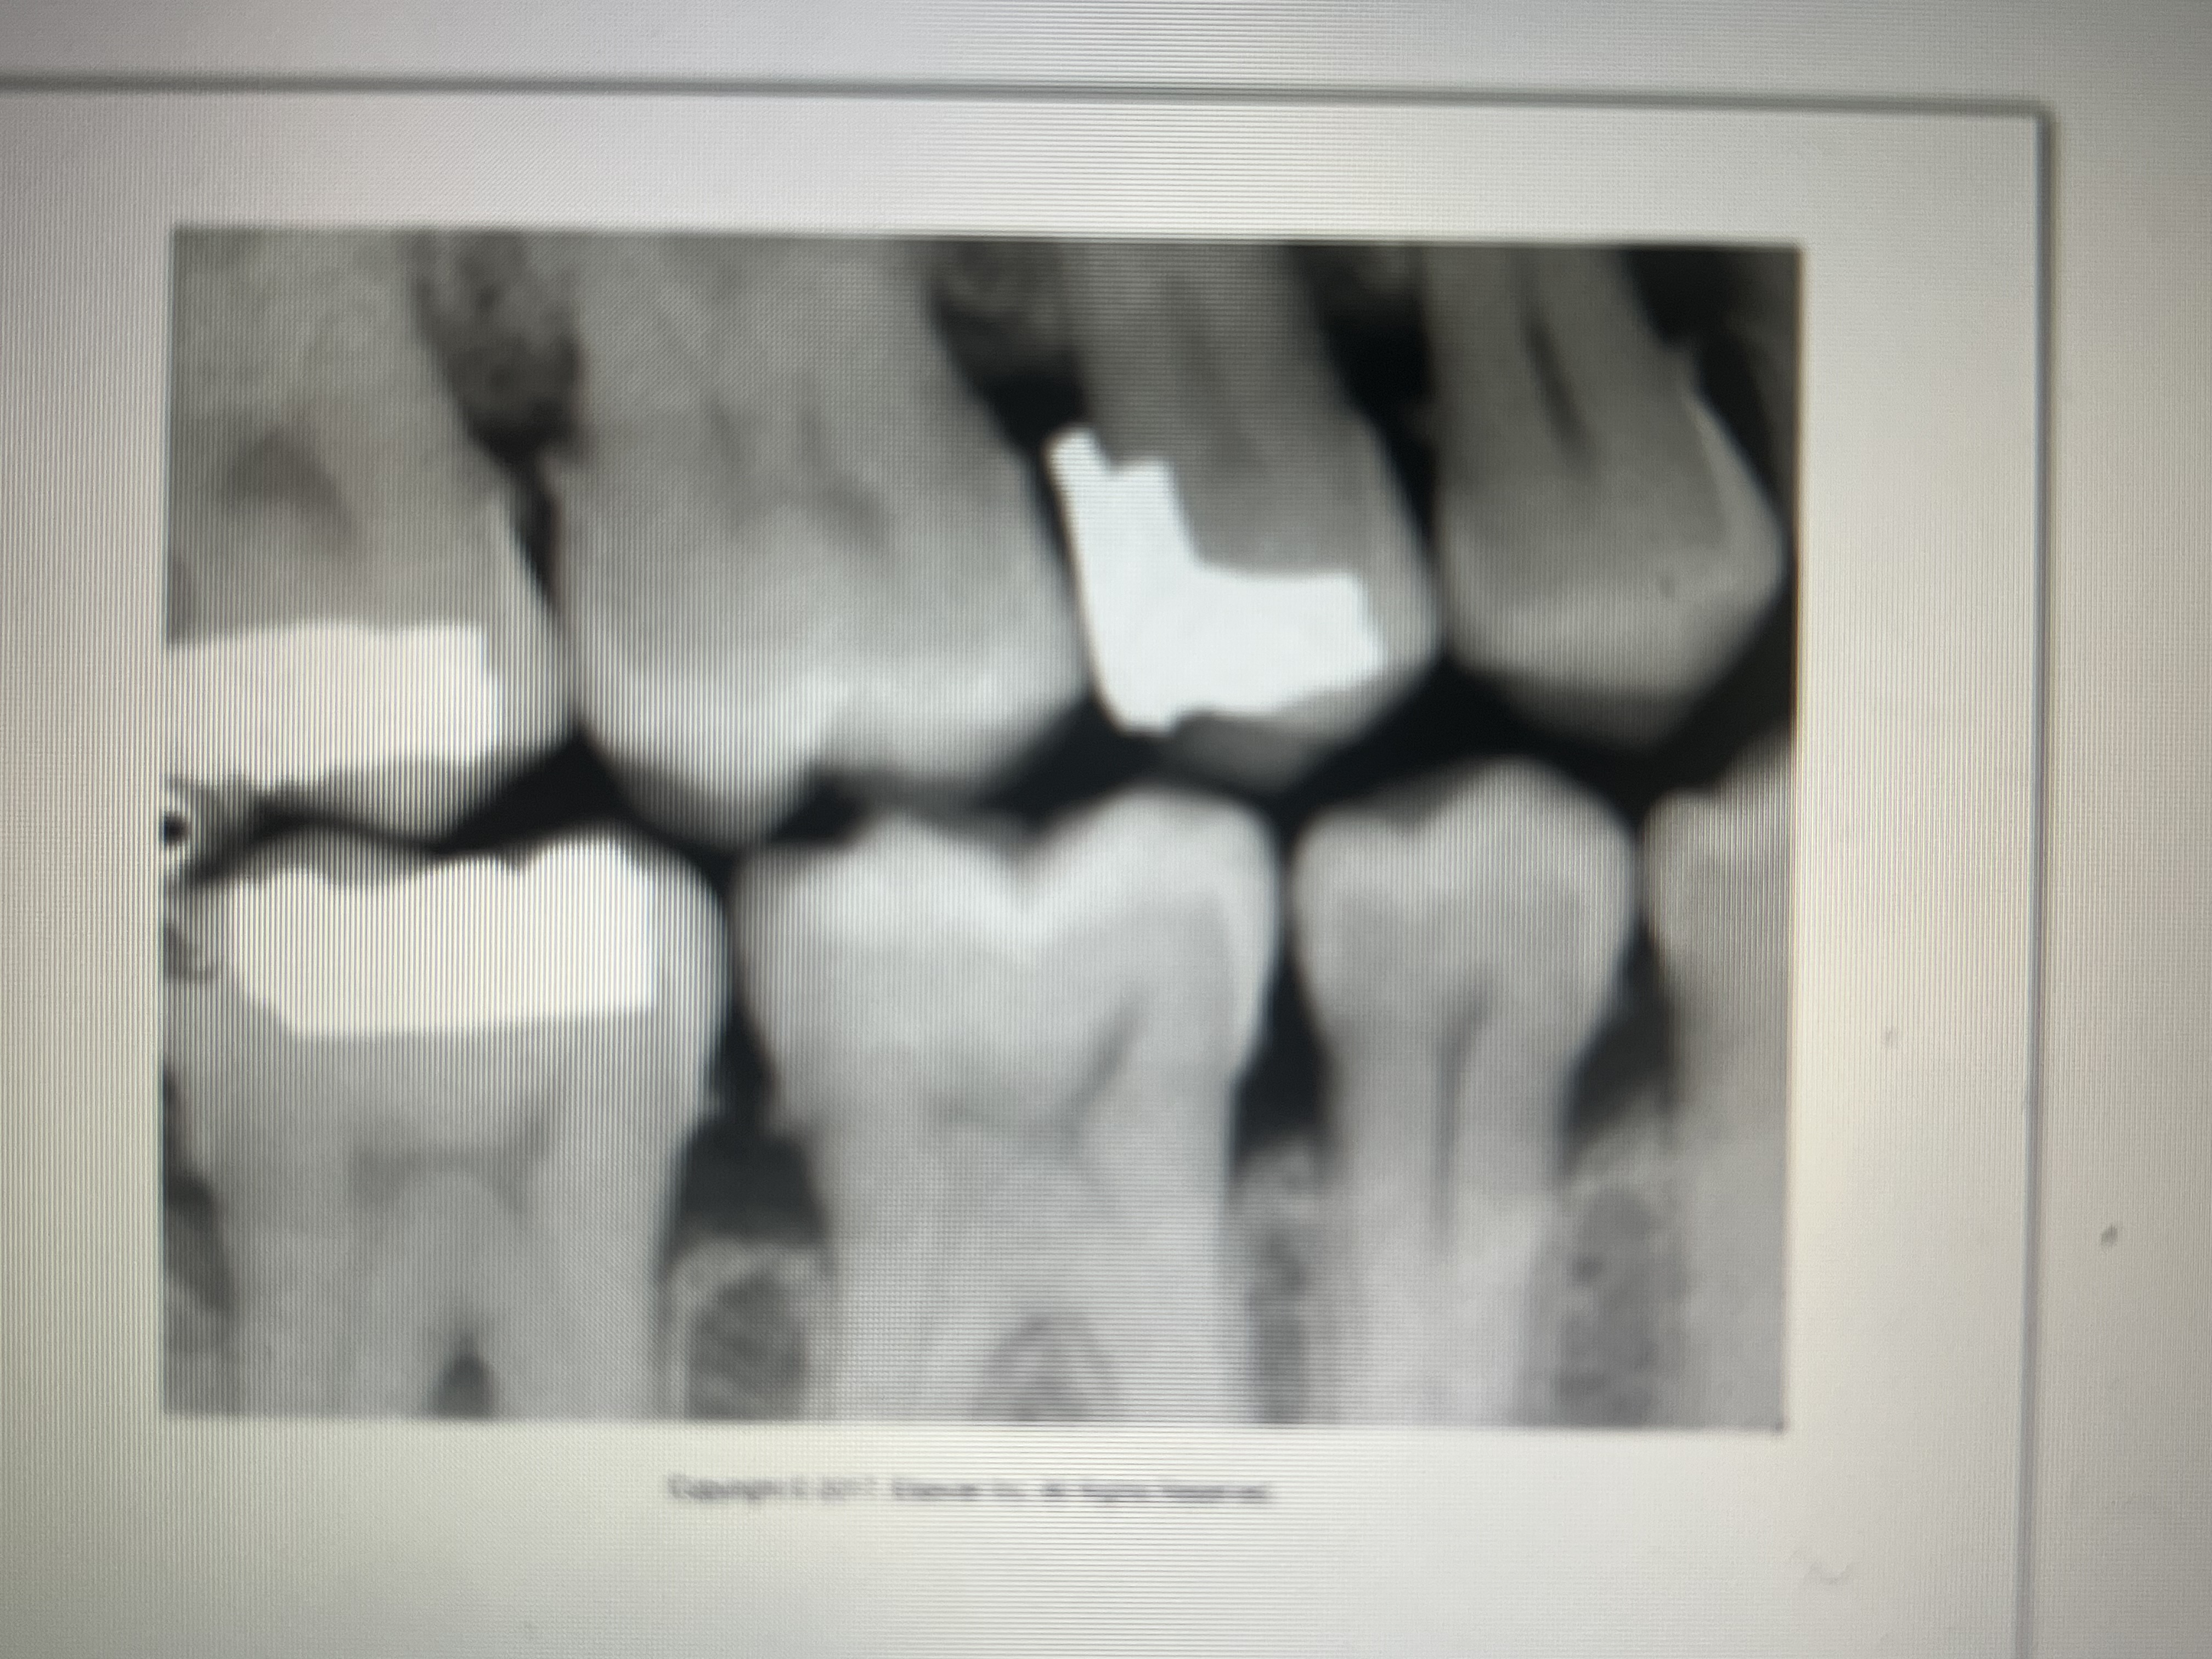

What does a PFM look like on a dental image?

metal component: completely radiopaque

porcelain component: slight radiopaque

How does an endosteal implant appear on a dental image?

Radiopaque